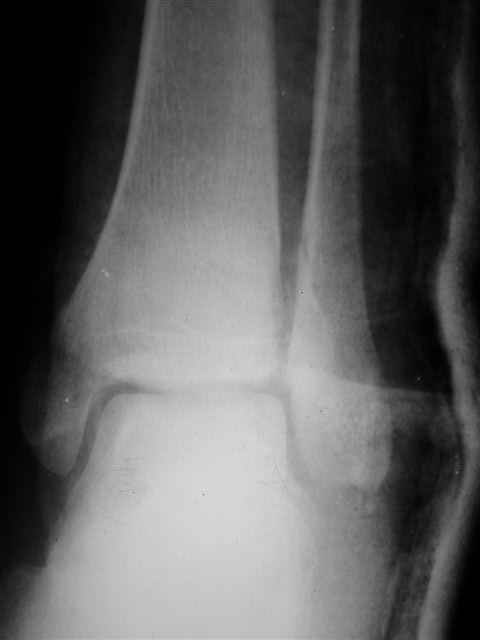

> Если Вас не затруднит, пришлите, пожалуйста, рентгенограммы. Я

> интересуюсь тактикой лечения повреждений голеностопного сустава.

> Хочется посмотреть, как лечат коллеги.

Ничего сверхъестественного, но если есть интерес, то в понедельник пересниму Рг-граммы и отправлю.

Уважаемый Иван,

Я предупреждал, что ничего сверхъестественного. Каюсь, что одна из спиц прошла несколько дальше, чем нужно было, но главное - перелом стабилизирован и больной работает суставом в полном объёме, несмотря на представленную раннее травму коленного сустава.